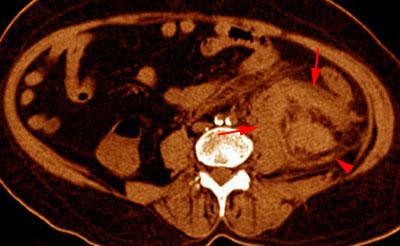

Hematoma subcapsular y perirrenal

VR seccional. Visión axial caudal. Exploración no contrastada que muestra un hematoma en el espacio perirrenal (flechas).Obsérvese la infiltración hemática de la cápsula de Gerota (punta de flecha)